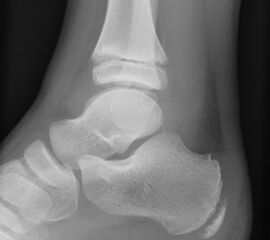

Welche minimalinvasiven fußchirurgischen Techniken in der Versorgung von Kinder- und Jugendfüßen geeignet und welche Indikationen sinnvoll sind, ist im Vergleich zu ausgewachsenen Füßen leicht abweichend. Hauptursache hierfür sind die Wachstumsfugen (Abb. 1).

Abb.1 a-b: Beispiel einer noch offenen Wachstumsfuge im dorsalen Bereich des Calcaneus: (a) Alter 6 und (b) Alter 9 Jahre.

In der Regel bestehen aktive Wachstumsfugen bei Mädchen bis zum 12. und bei Jungen bis zum 14. Lebensjahr, mit Abweichungen von einem Jahr nach unten und nach oben. Präzise Informationen unter anderem darüber gibt das präoperative Röntgenbild (Abb. 2).